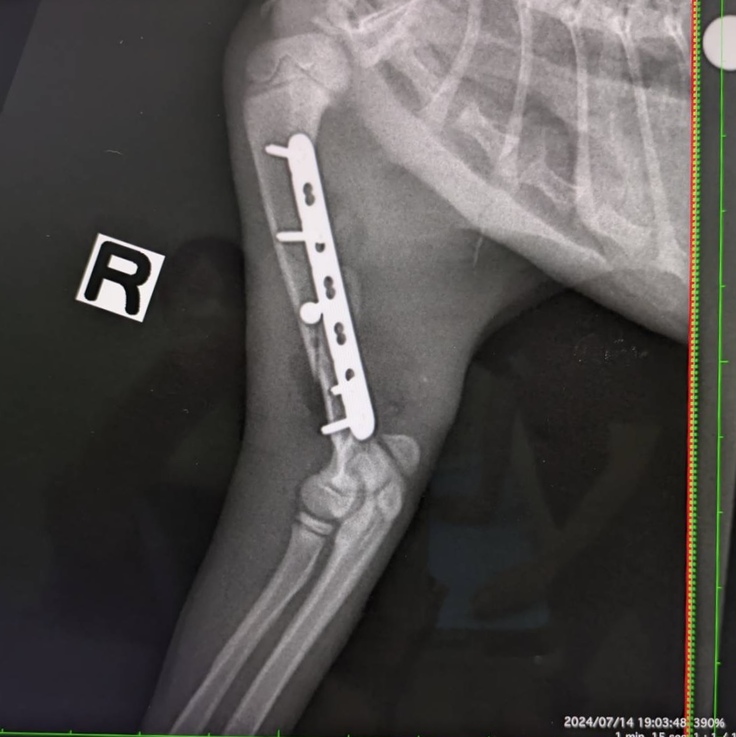

右上腕

左下腿

7月14日病院より連絡があり、上腕骨の骨が想定より皮膚一枚のところにあるため、早急に腕だけ手術をしたいとのことでした。血液検査の結果は問題なく呼吸状態も良い、タビちゃんも食欲があり手術に耐え得るであろうという判断のもと、手術となりました。

右上腕術後のレントゲン